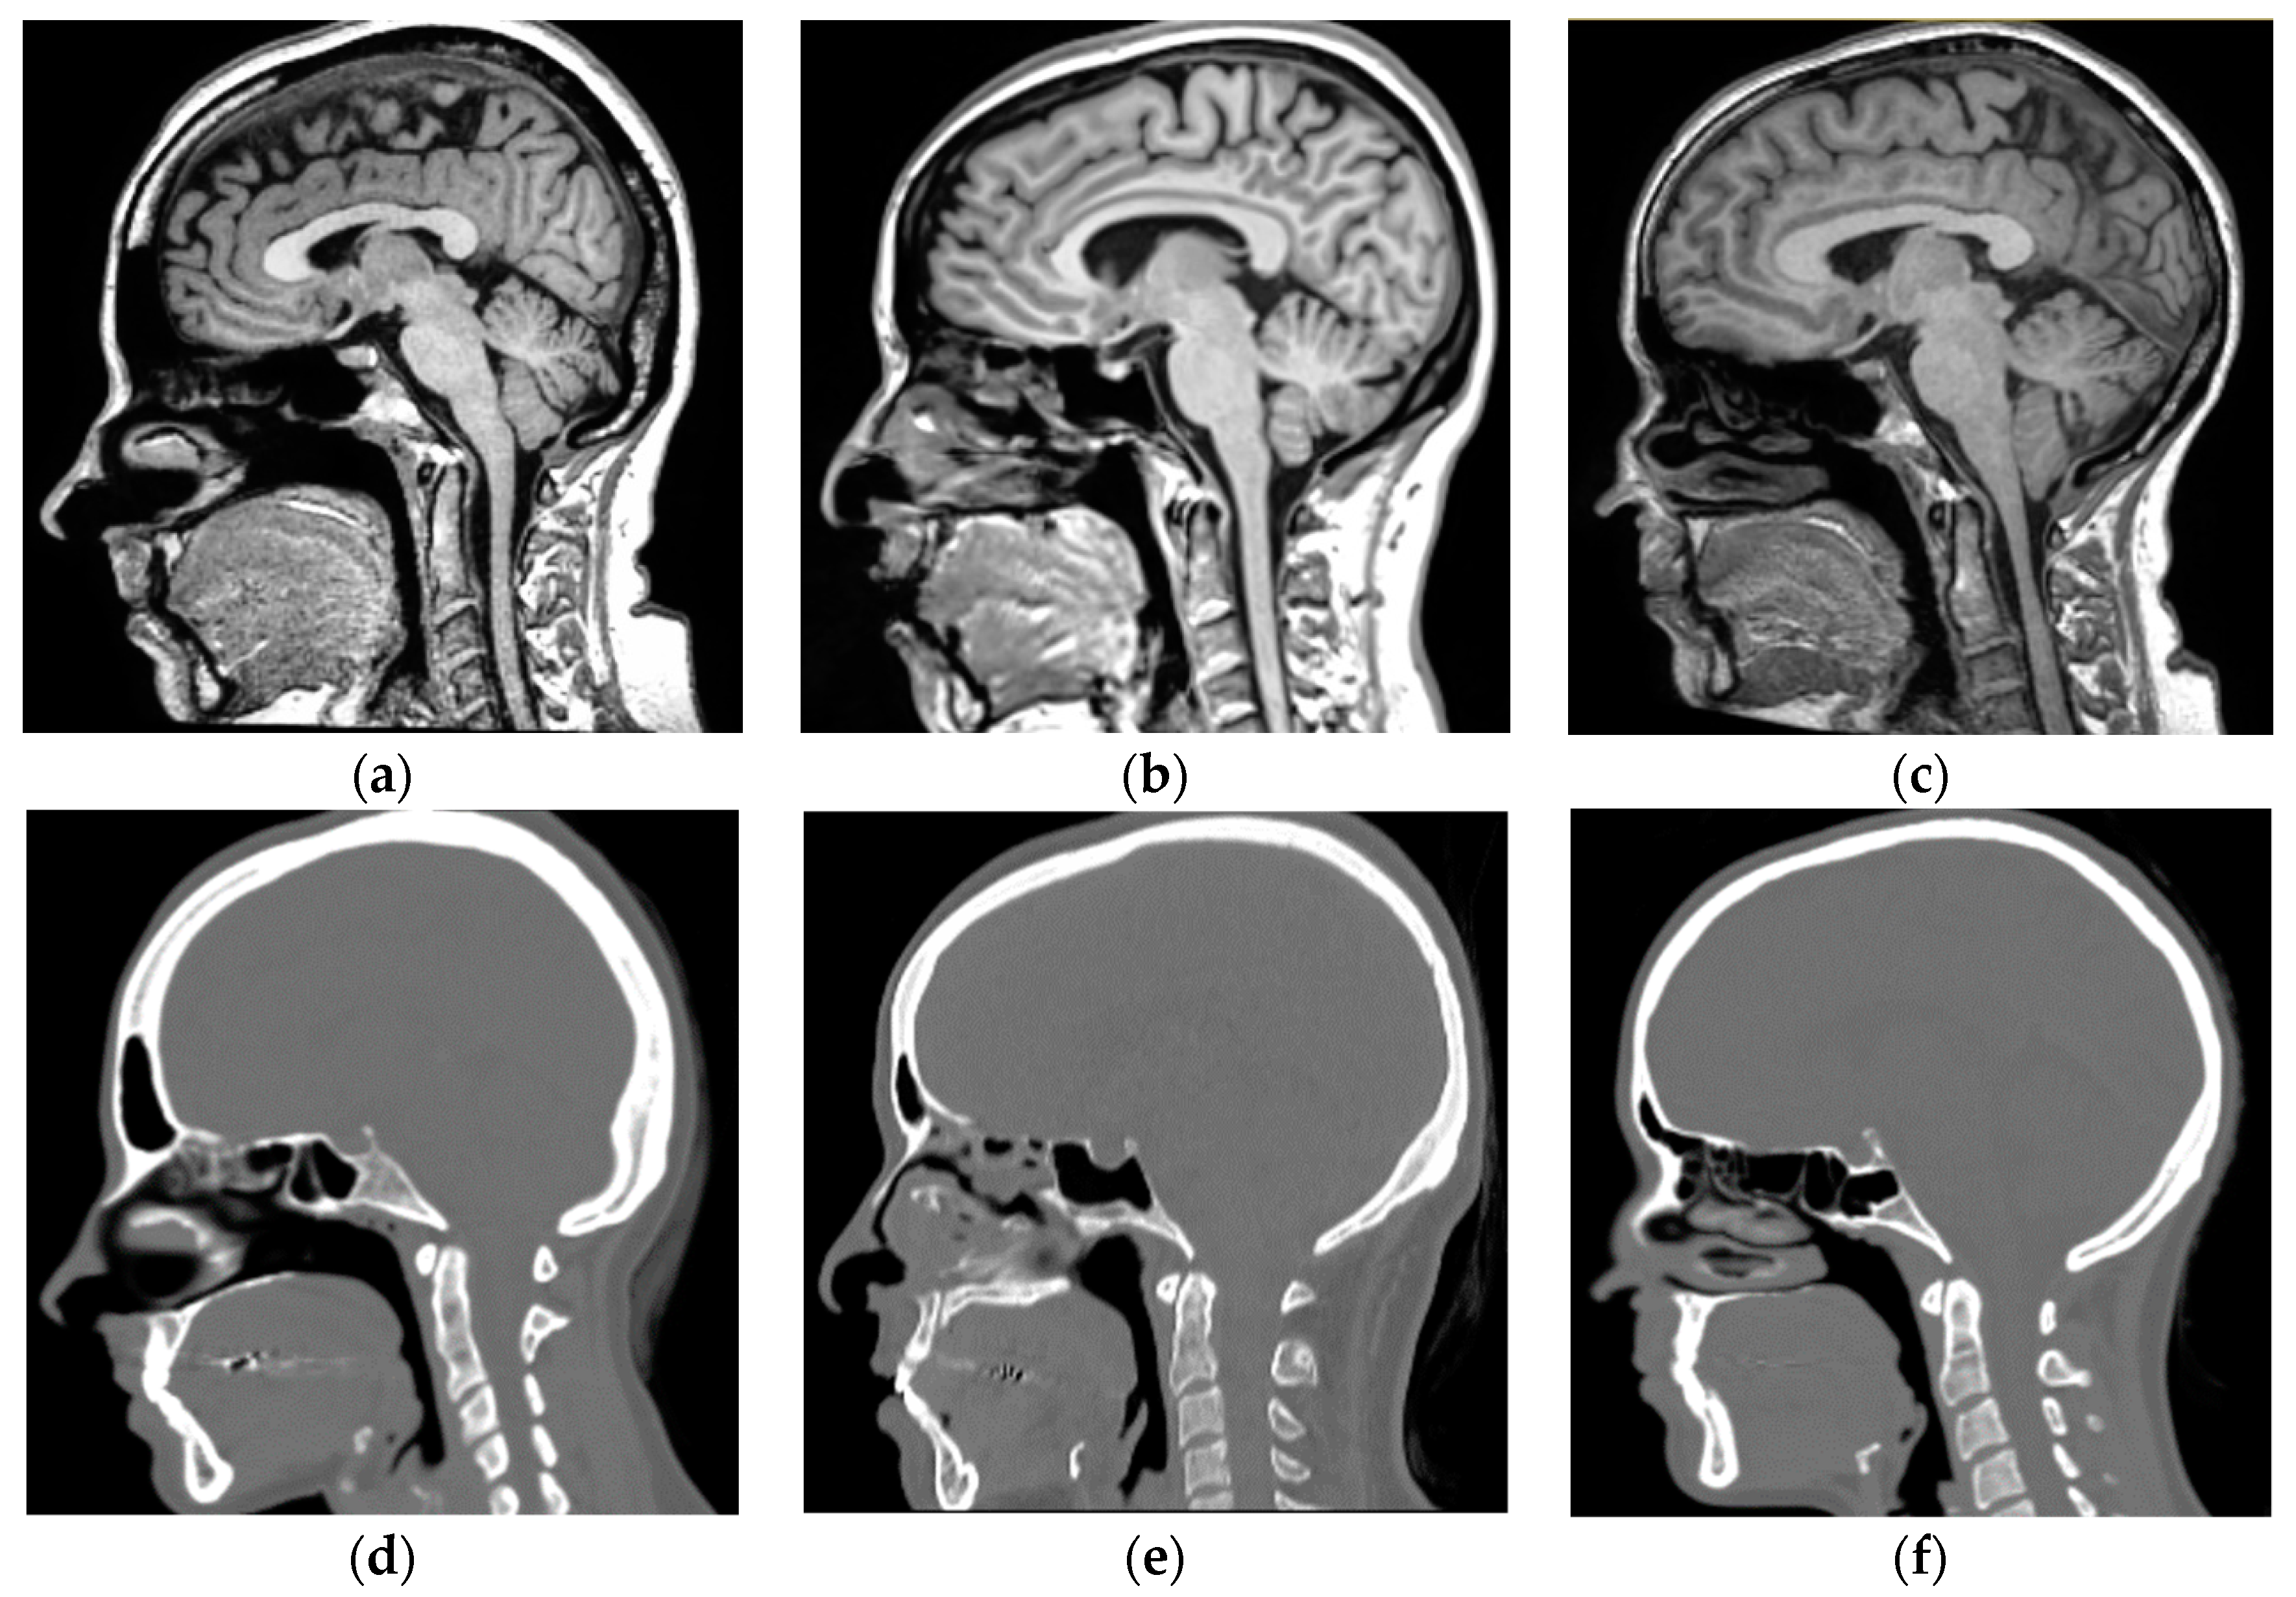

2.2.3. Datasets Preprocessing

- Resampling of MR and CT images to an isotropic 1 mm space was performed (Resample Scalar Volume, 3D Slicer) to set a common resolution space for all images ((271, 271, 221) pixels) and avoid information loss in the following steps.

- Intra-patient rigid registration to align each MR-CT pair. The method consists of an initial manual registration using characteristic points (Fiducial Registration Wizard, 3D Slicer), an automatic rigid registration step (General Registration Brains, 3D Slicer), and a manual adjustment of the registration (Transforms, 3D Slicer). This is a crucial step and guarantees the correspondence between each anatomical point of both image techniques.

- Reslicing and crop all MR and CT images to a reference image (Resample Image Brains, 3D Slicer) to ensure the same matrix size prior training our network.

- MR-CT image information matching (MATLAB, MathWorks Inc.) to ensure there is no MR or CT information in areas where one of the modalities is out of the other, so as to ensure that the same anatomical area is represented in both MR and CT.